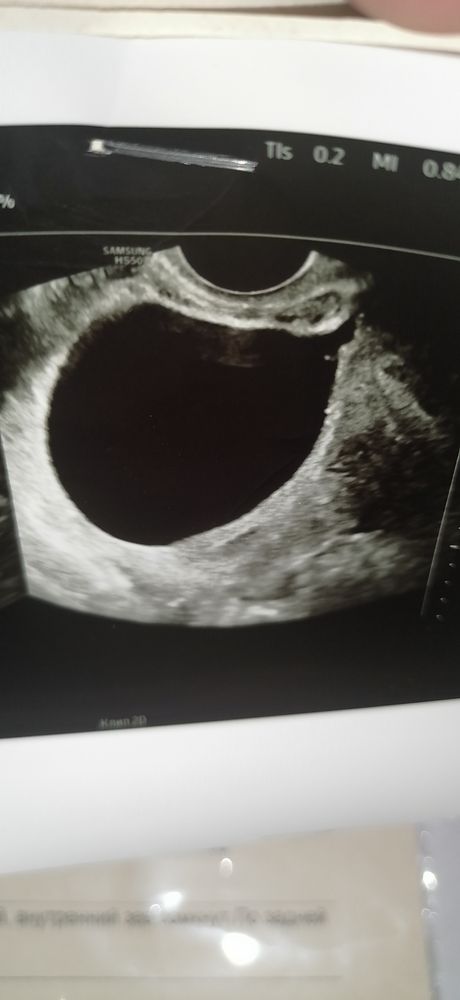

ИзображениеИзображение Александра Катаева, здесь разве что то есть? Это узи 13 числа, ПЯ 11мм, ЖМ 3,9мм

Екатерина, честно говоря, здесь не очень удачный ракрус для оценки... То ли доктор слишком увеличил... то ли срез не тот. Но, наверняка, были и другие. Думаю, самое разумное - верить протоколу, настраиваться на хорошее и ждать четверга. Ждать и догонять хуже всего... )) Но там уж точки над i точно будут расставлены))

Анэмбрионию ставят, если в плодном яйце больше 13 мм нет желточного мешка или в плодном яйце больше 25 мм нет эмбриона. У вас все хорошо, даже желточный мешочек уже есть, вы просто рано пошли на УЗИ.

Екатерина Орлова, у вас все идёт нормально, и желточный мешочек есть и он нормальных размеров, в полном яйце такого размера эмбрион редко находят. У меня старшего нашли, когда пя уже 17мм было.